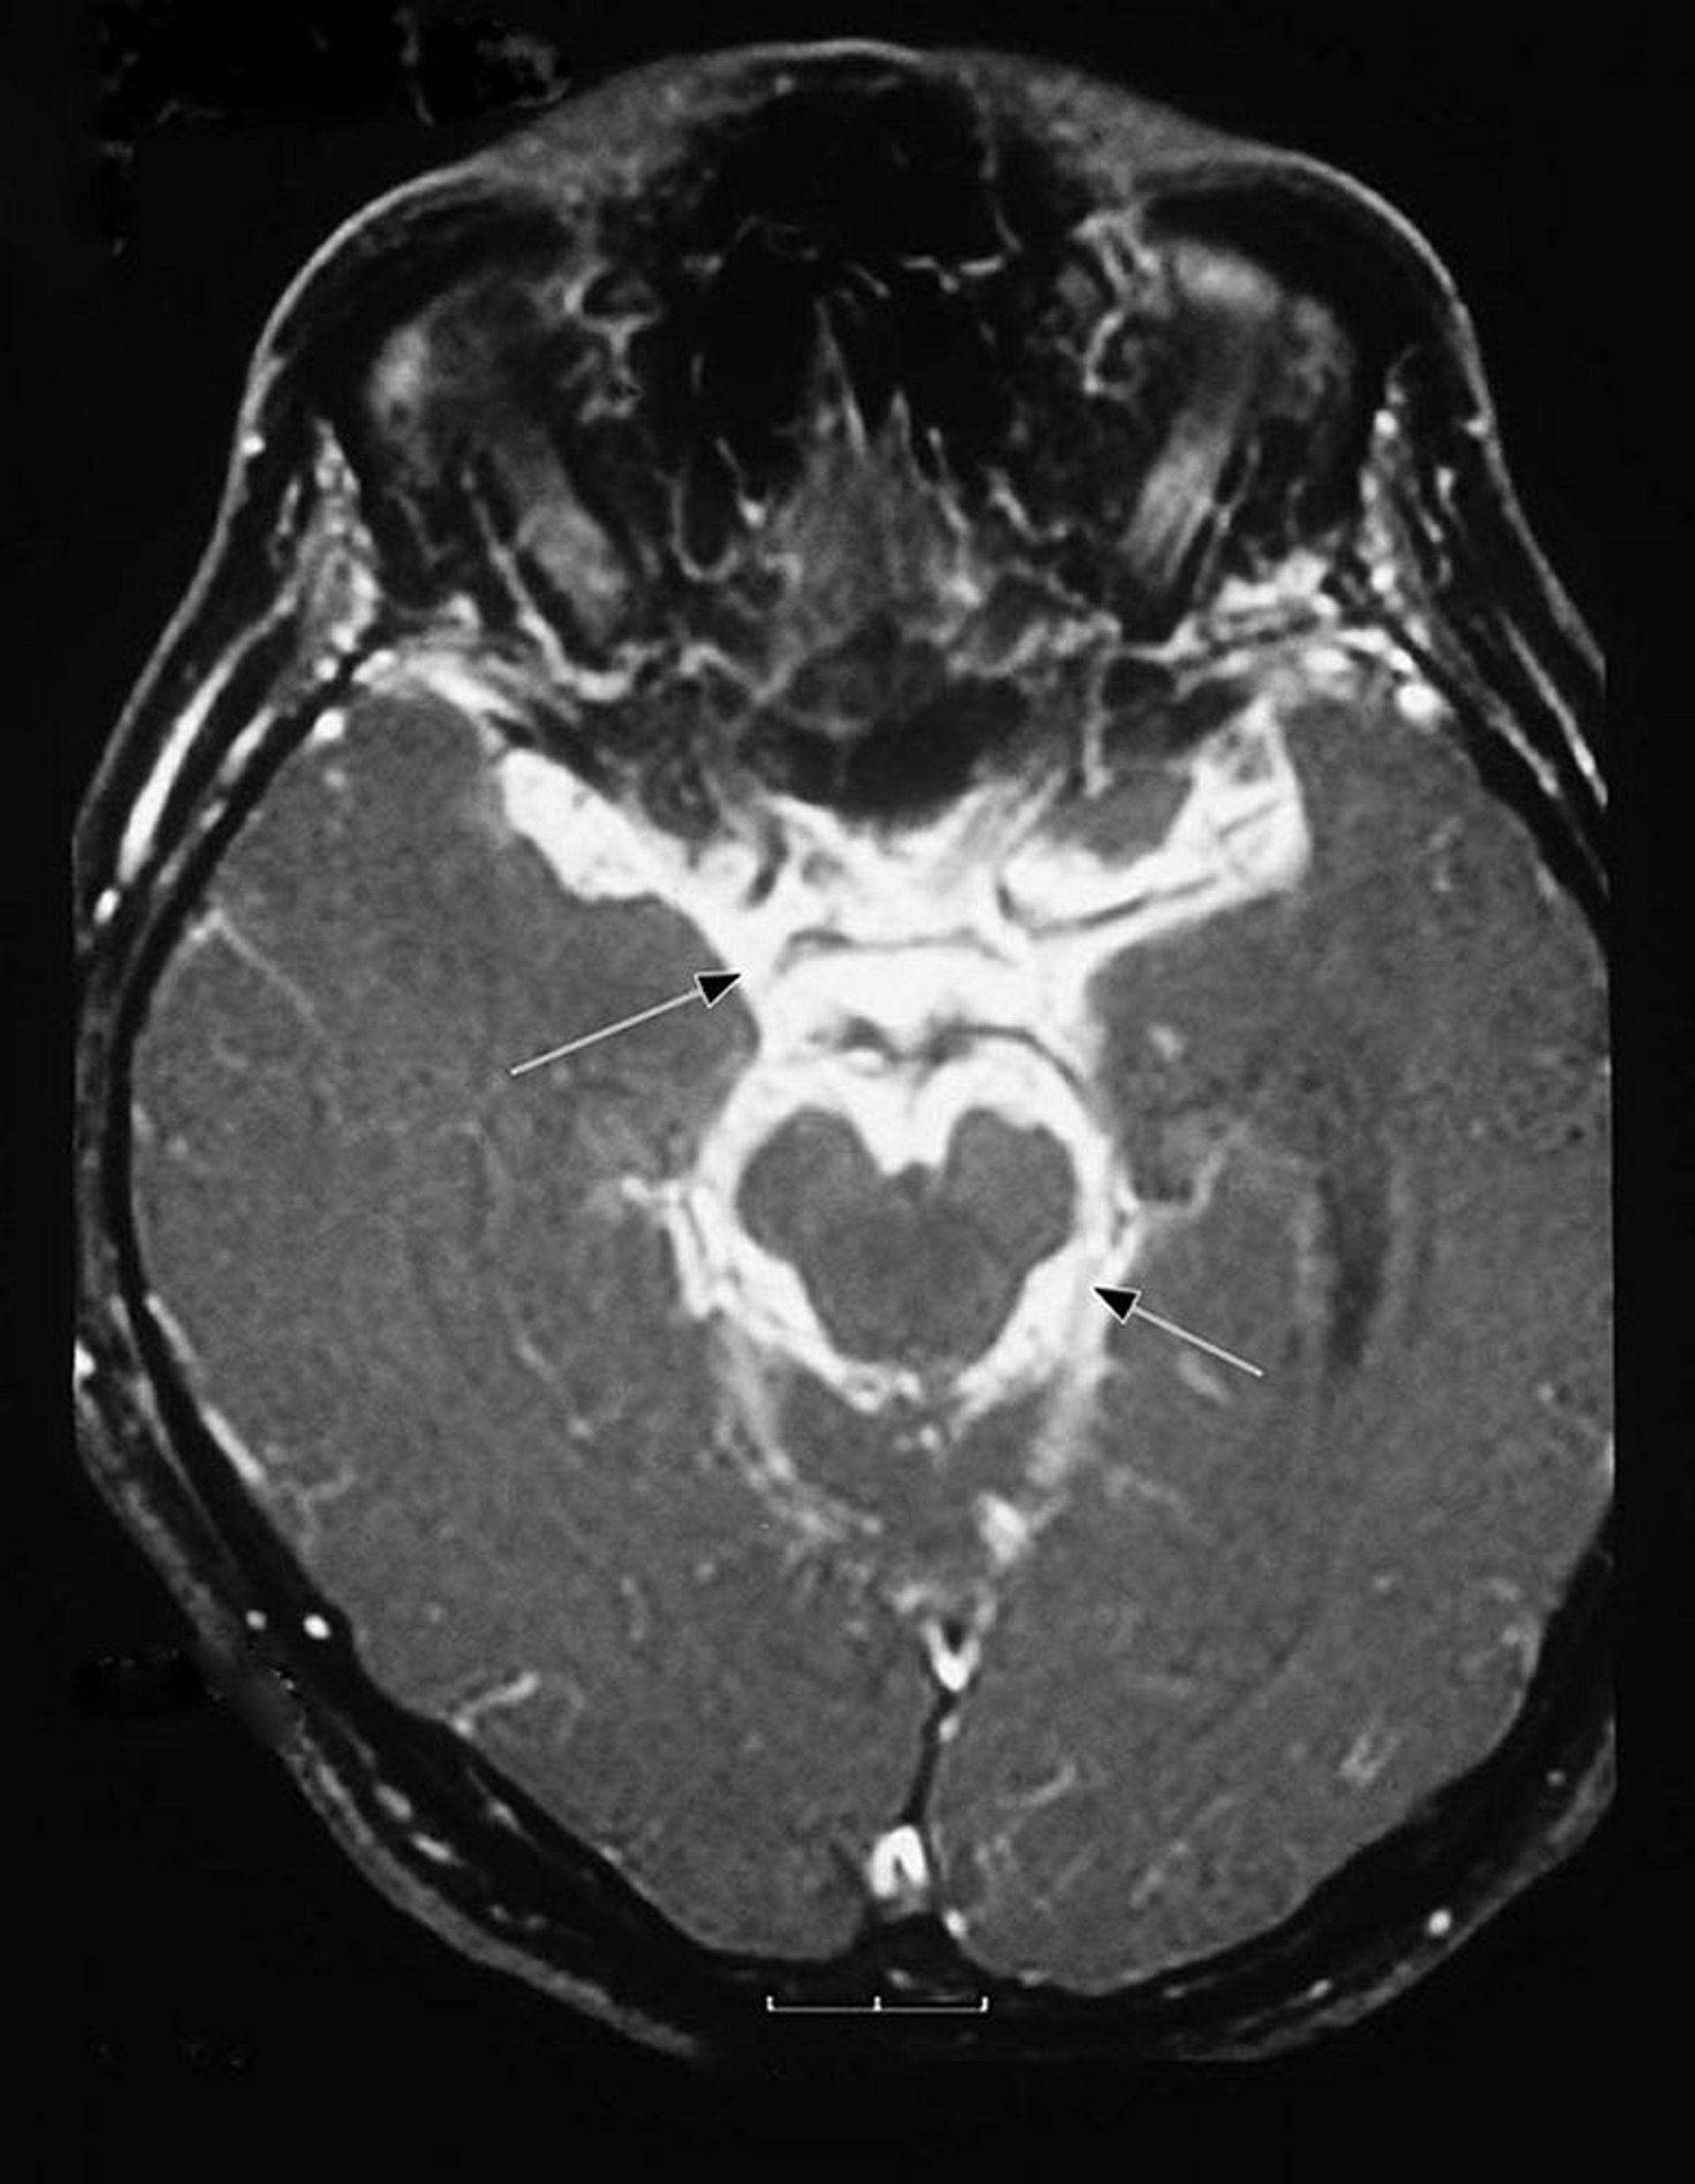

Méningite tuberculeuse

Cette imagerie par résonance magnétique (IRM) d'un patient atteint de méningite tuberculeuse montre un exsudat inflammatoire intense à la base du cerveau (méninges basilaires [flèches]) et entourant le tronc cérébral.

Image courtoisie de John E. Greenlee, MD.